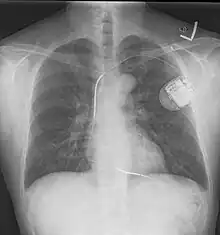

Chest radiograph

A normal posteroanterior (PA) chest radiograph of someone without any signs of injury. Dx and Sin stand for "right" and "left" respectively.

A chest radiograph, called a chest X-ray (CXR), or chest film, is a projection radiograph of the chest used to diagnose conditions affecting the chest, its contents, and nearby structures. Chest radiographs are the most common film taken in medicine.